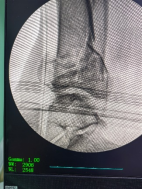

透視檢查骨折端

控制機器人牽引斷端,可見關(guān)節(jié)間隙恢復。